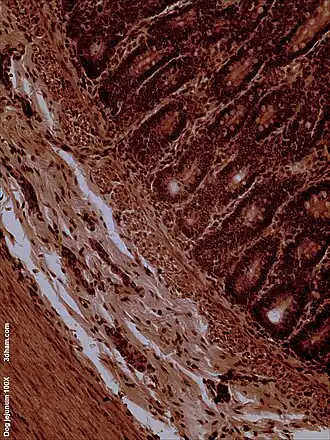

La superficie interna del yeyuno, formada por una membrana mucosa, está cubierta en las proyecciones llamadas vellosidades, que aumentan la superficie de tejidos disponibles para absorber los nutrientes de los alimentos previamente digeridos por el estómago. Las células anales epiteliales que recubren estas vellosidades tienen un número aún mayor de microvellosidades. Son las vellosidades y las microvellosidades las que permiten que en una pequeña porción de tubo digestivo, se absorba una gran cantidad de nutrientes. El transporte de nutrientes a través de las células epiteliales a través del yeyuno y el íleon incluye el transporte pasivo de la fructosa, el azúcar y el transporte activo de aminoácidos, péptidos pequeños, vitaminas, y la mayoría de la glucosa. El ácido fólico, metabolito esencial del ciclo celular, es absorbido principalmente a este nivel del intestino delgado. Las vellosidades en el yeyuno son mucho más largas que en el duodeno o el íleon.

Microscopía electrónica del yeyuno -

ME del yeyuno de un ratón x14000